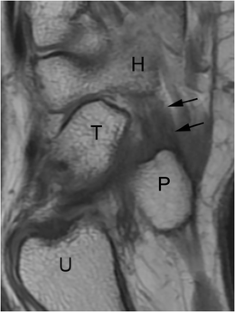

Fig. 1